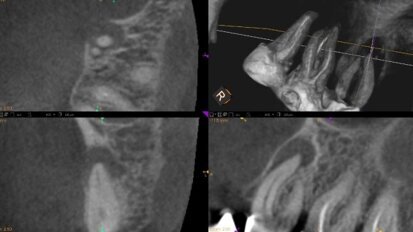

„3D w endodoncji – jak diagnozować i leczyć bezpiecznie” – webinarium DT Study Club!

Dental Tribune Study Club zaprasza do udziału w webinarium, które odbędzie się w poniedziałek 5 grudnia o godz. 20.00. Wykład pt.: „3D w ...